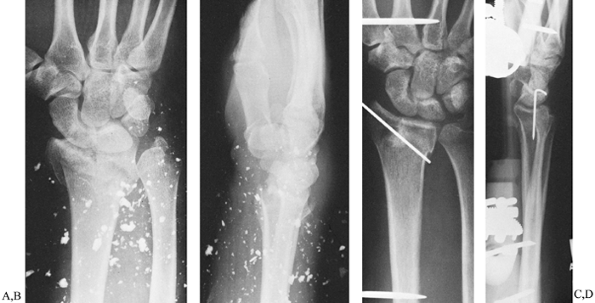

![]() |

|

Figure 44.6. Comminuted distal radius fracture sustained in car accident with metal particles imbedded in the skin. A,B: Preoperative radiographs, anteroposterior and lateral views. C,D:

Postoperative radiographs, anteroposterior and lateral views, demonstrating application of external fixation with supplemental percutaneous pin fixation. The external fixation device used in this case was a WristJack. |